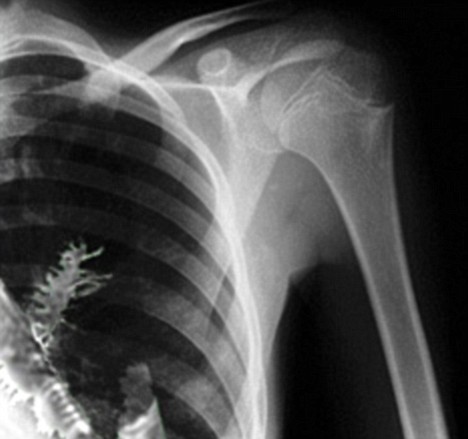

Doctors operating on 28-year-old Artyom Sidorkin was expecting to find a tumor in one of his lungs, but they got a big, green surprise during the surgery:

Doctors x-rayed his chest and found a tumor in one of the lungs. Suspecting cancer, they made a decision to perform biopsy, but when they cut the tissue, they were amazed to see green needles in the cut.

new x-ray pic